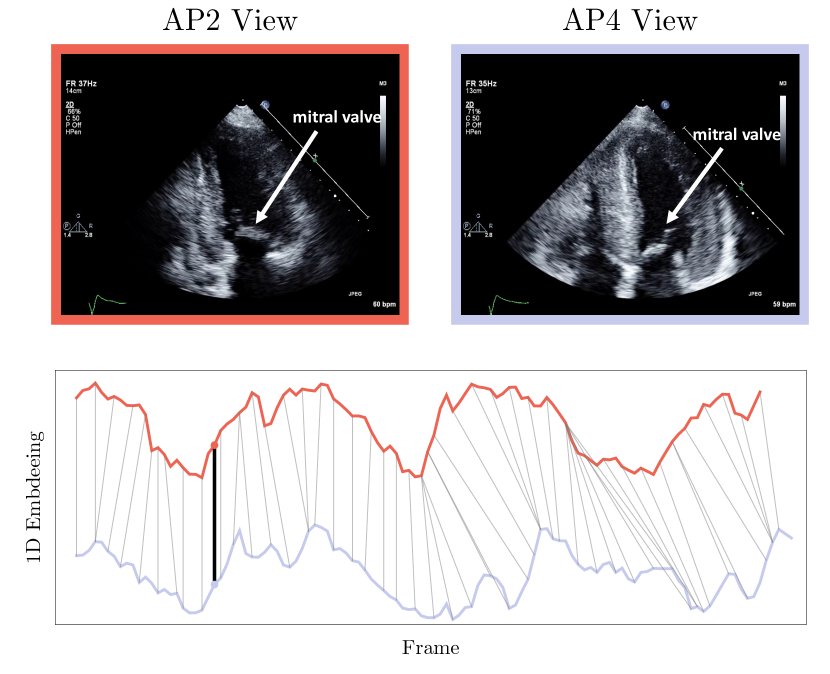

In Figure 6, the synchronization of an AP4 and AP2 echo cine is shown. To examine the details of the synchronization keyframes showing the max contraction of the left ventricle and the opening/closing of the mitral valve are shown. Additionally, we show the dynamic time warping correspondence between the embeddings of the two cines. Further information on the visualization of the cine embeddings in Figure 6 and the supplementary material is explained in Figure 7.

Refer to caption

Figure 6: A sample synchronization produced by Echo-SyncNet. We examine the synchronization of an AP4 and AP2 echo cine by comparing three distinct cardiac events: the earliest opening of the mitral valve, the maximum contraction of the left ventricle and the earliest closing of the mitral valve. We show the correspondence of these three cardiac events on the respective embeddings generated by Echo-SyncNet — AP4 (red), AP2 (blue). Additionally, a full mapping between the AP4 and AP2 embeddings is shown with thin gray lines. Please see the supplementary files for synchronized video results.

Figure 7: Visualization of embeddings: For each view, we show trajectories of the cines in the embedding space. Using a principal component analysis reduction approach, we reduce the dimensionality of the embedding from 128 to 1 for visualization. The visualization indicates how the embeddings change as the cardiac cycle progresses and how two cines with a different number of frames can be synced together. The images show a sample correspondence point (shown with black line in the lower sub-figure) for an AP4 and AP2 cardiac echo as well as their respective embeddings. Notice the corresponding position of the mitral valve in both images, and for a more obvious correspondence of cardiac walls and chambers during a cardiac cycle please see the supplementary videos.